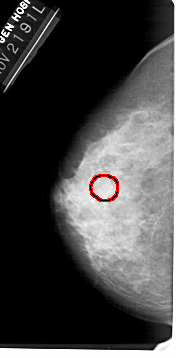

A_1449_1.LEFT_CC

LEFT_CC LINES 5356 PIXELS_PER_LINE 2626 BITS_PER_PIXEL 12 RESOLUTION 43.5 OVERLAY

FILE: A_1449_1.LEFT_CC.OVERLAY

TOTAL_ABNORMALITIES 1

ABNORMALITY 1

LESION_TYPE CALCIFICATION TYPE AMORPHOUS DISTRIBUTION CLUSTERED

ASSESSMENT 4

SUBTLETY 2

PATHOLOGY BENIGN

TOTAL_OUTLINES 1